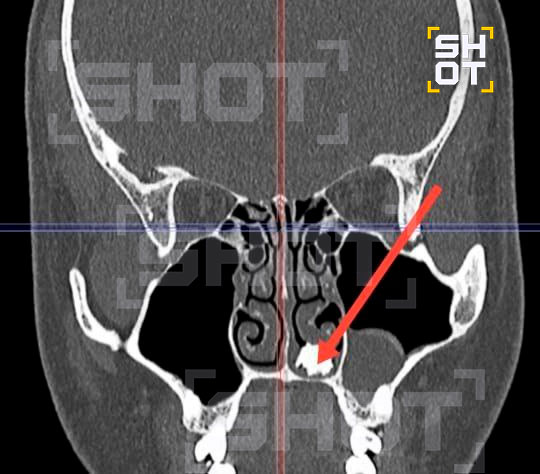

Парень из Подмосковья несколько месяцев жил с молочным зубом в носу

По данным SHOT, 22-летний бедолага долго не мог вылечить насморк и обратился в Долгопрудненскую больницу. Там врачи проявили диагностику и нашли в носу странный предмет. Парня срочно отправили на операцию.

Оказалось, дышать полной грудью ему мешал молочный зуб, который каким-то образом оказался не на своём месте. Его быстро извлекли, а парня через несколько дней выписали.